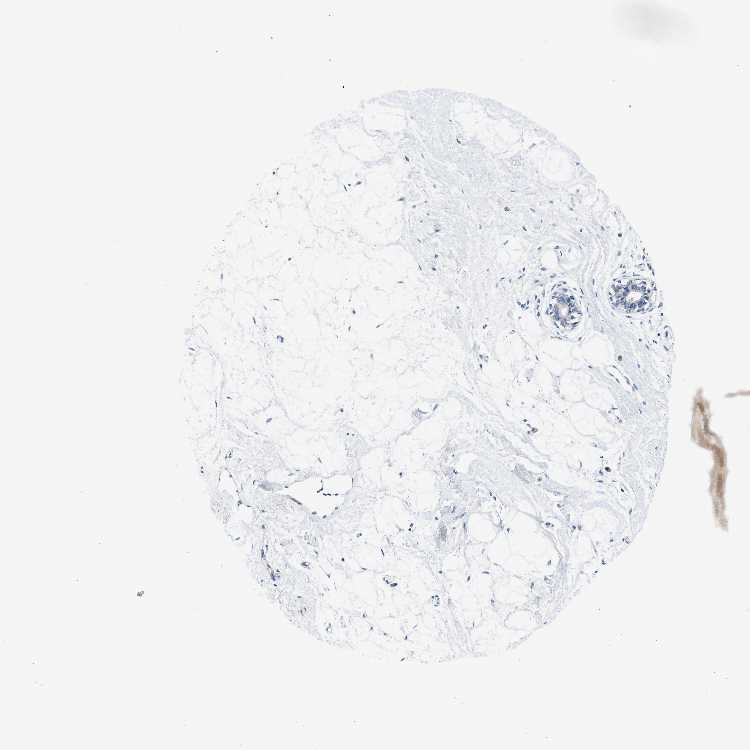

BREAST - Antibody stainingi

Antibody staining in the annotated cell types in the current human tissue is reported as not detected, low, medium, or high, based on conventional immunohistochemistry profiling in selected tissues. This score is based on the combination of the staining intensity and fraction of stained cells.

Each image is clickable and will lead to virtual microscopy that enables deeper exploration of all samples and also displays staining intensity scores, fraction scores and subcellular localization as well as patient and tissue information for each sample.

Antibody HPA016802

Adipocytes Not detected

Glandular cells Not detected

Myoepithelial cells Not detected